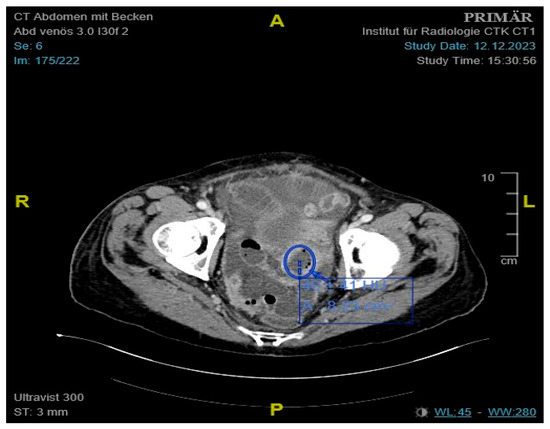

Initial labs showed microcytic anemia with suspicion of iron deficiency. Abdominal ultrasound showed marked ascites and findings suggestive of peritoneal carcinomatosis. A CT of the abdomen revealed a small bowel conglomerate tumor (Figure 1) and enlarged paraaortic lymph nodes. Chest CT demonstrated bilateral scattered consolidations suspicious for metastatic spread (Figure 2). Bronchoscopy was unremarkable, and direct microscopy was negative for AFB. Subsequently, the patient developed a small bowel ileus, raising suspicion for a jejunal tumor. During the subsequent emergent laparoscopy, we observed a conglomeration tumor consisting of the loops of the small intestine. Emergency laparoscopy revealed a small bowel conglomerate mass, and the biopsy from the lower abdomen showed caseating granulomatous peritonitis (Figure 3). A detailed history revealed her partner had previously been diagnosed with pulmonary tuberculosis caused by Mycobacterium chimaera. The patient had no follow-up for TB because her partner was considered not infectious.

Figure 1. Contrast-enhanced CT of the abdomen showing an approximately 4.1 cm mass, consistent with a small bowel conglomerate tumor.